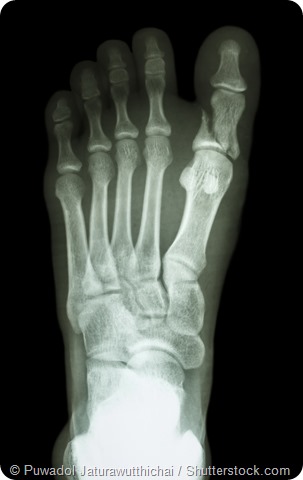

Fractured foot x-ray

X-ray showing fracture of proximal phalange at first toe